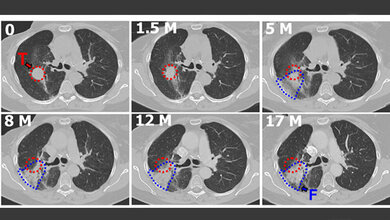

Während in die Lunge eingedrungene Fremdpartikel normalerweise durch Flimmerhärchen abgefangen, zurück in die Atemwege transportiert und ausgehustet werden, können feine Fasern wie Asbest bis tief in die Lungenbläschen vordringen. Als Reaktion der Lunge können sich geflechtartig-netzähnliche diffuse Vernarbungen mit den darin eingelagerten Stäuben bilden, die sogenannte Asbestose. Da die Asbestfaser so biobeständig ist, können die Fresszellen des Immunsystems sie nicht abbauen. Diese Fresszellen sterben ab und bilden die typischen Asbestkörper. Dabei werden Inhaltsstoffe frei, die eine chronische Entzündung verursachen, woraus Krebs entstehen kann. Zudem reichern sich in dieser Hüllstruktur Elemente an, die ebenfalls für die krebserzeugende Wirkung der Asbestkörper verantwortlich sein können.

Auch eine Lungentransplantation bei fortgeschrittener Fibrose kommt für Asbestose-Patienten in der Regel eher nicht in Betracht. „Im Röntgenbild sind nicht asbestbedingte Lungenfibrosen von einer Asbestose kaum zu unterscheiden“, erklärt Prof. Dr. Rolf Merget, Arbeitsmediziner am IPA. „Daher ist es von zentraler Bedeutung, dass Asbestfasern im Lungengewebe nach so langer Zeit noch nachweisbar sind.“ Nicht zuletzt ist die Frage der Nachweisbarkeit von Asbestfasern in der Lunge entscheidend dafür, wie man das Risiko durch Asbest am Arbeitsplatz bewertet. Daraus folgt die Entscheidung, ob eine Lungenerkrankung als Berufskrankheit anerkannt werden kann, sodass die Betroffenen Anspruch auf eine Entschädigung haben. (idw, red)